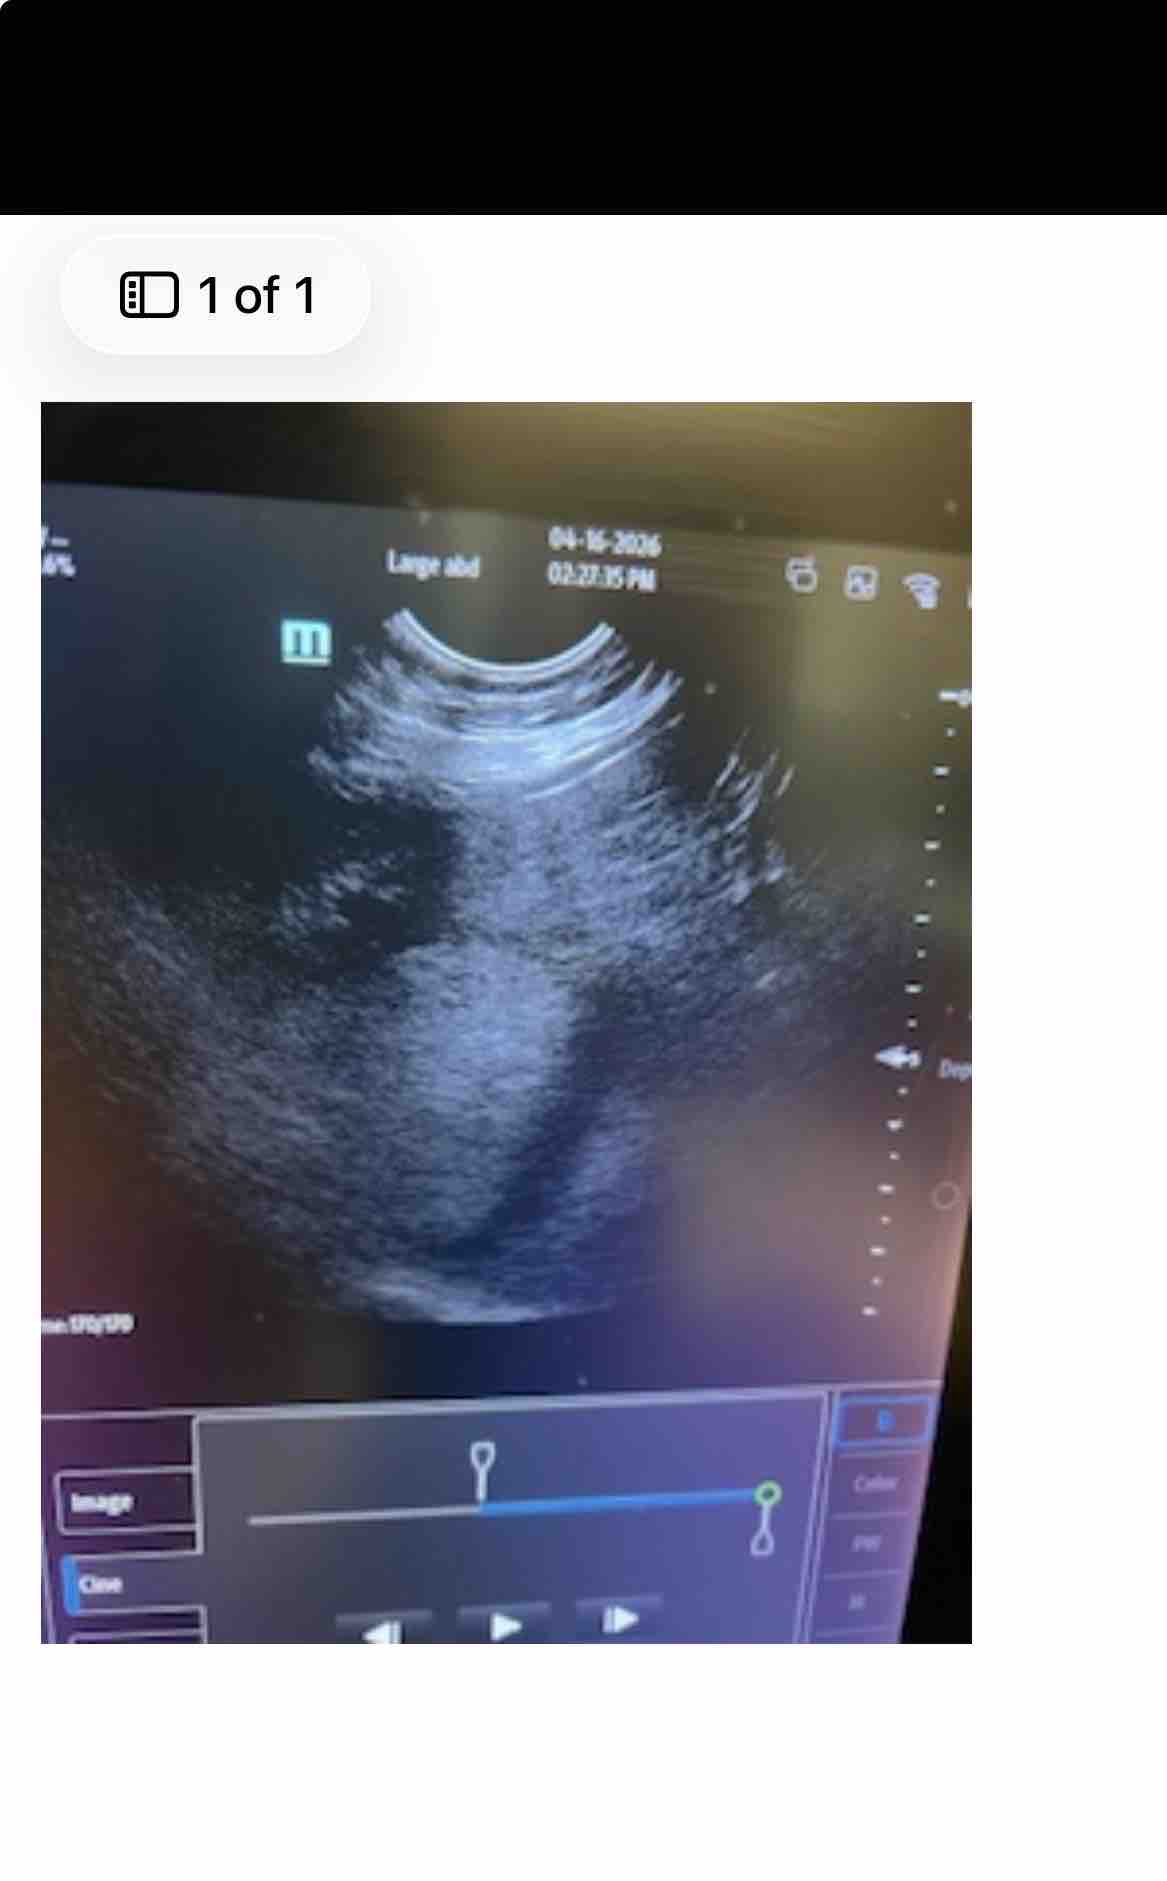

Tesla is my life, and recently she was diagnosed with a large liver tumor, likely cancer. The news caught me completely off guard, and the tumor is already squishing her organs. There are many steps ahead in this journey, and last week was just the beginning. On May 4, we'll learn much more—like whether she's a candidate for a potential lobectomy, which could give her a chance at recovery.